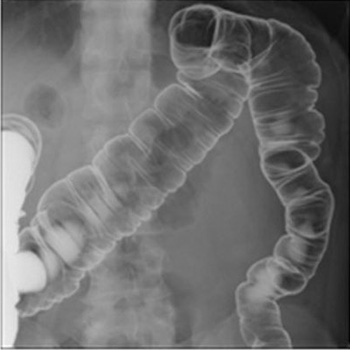

X線透視検査

X線をTVモニターに映像化し、リアルタイムの動画を見ながら検査や治療をおこなっています。バリウム検査や内視鏡検査、骨折整復などで使用しています。